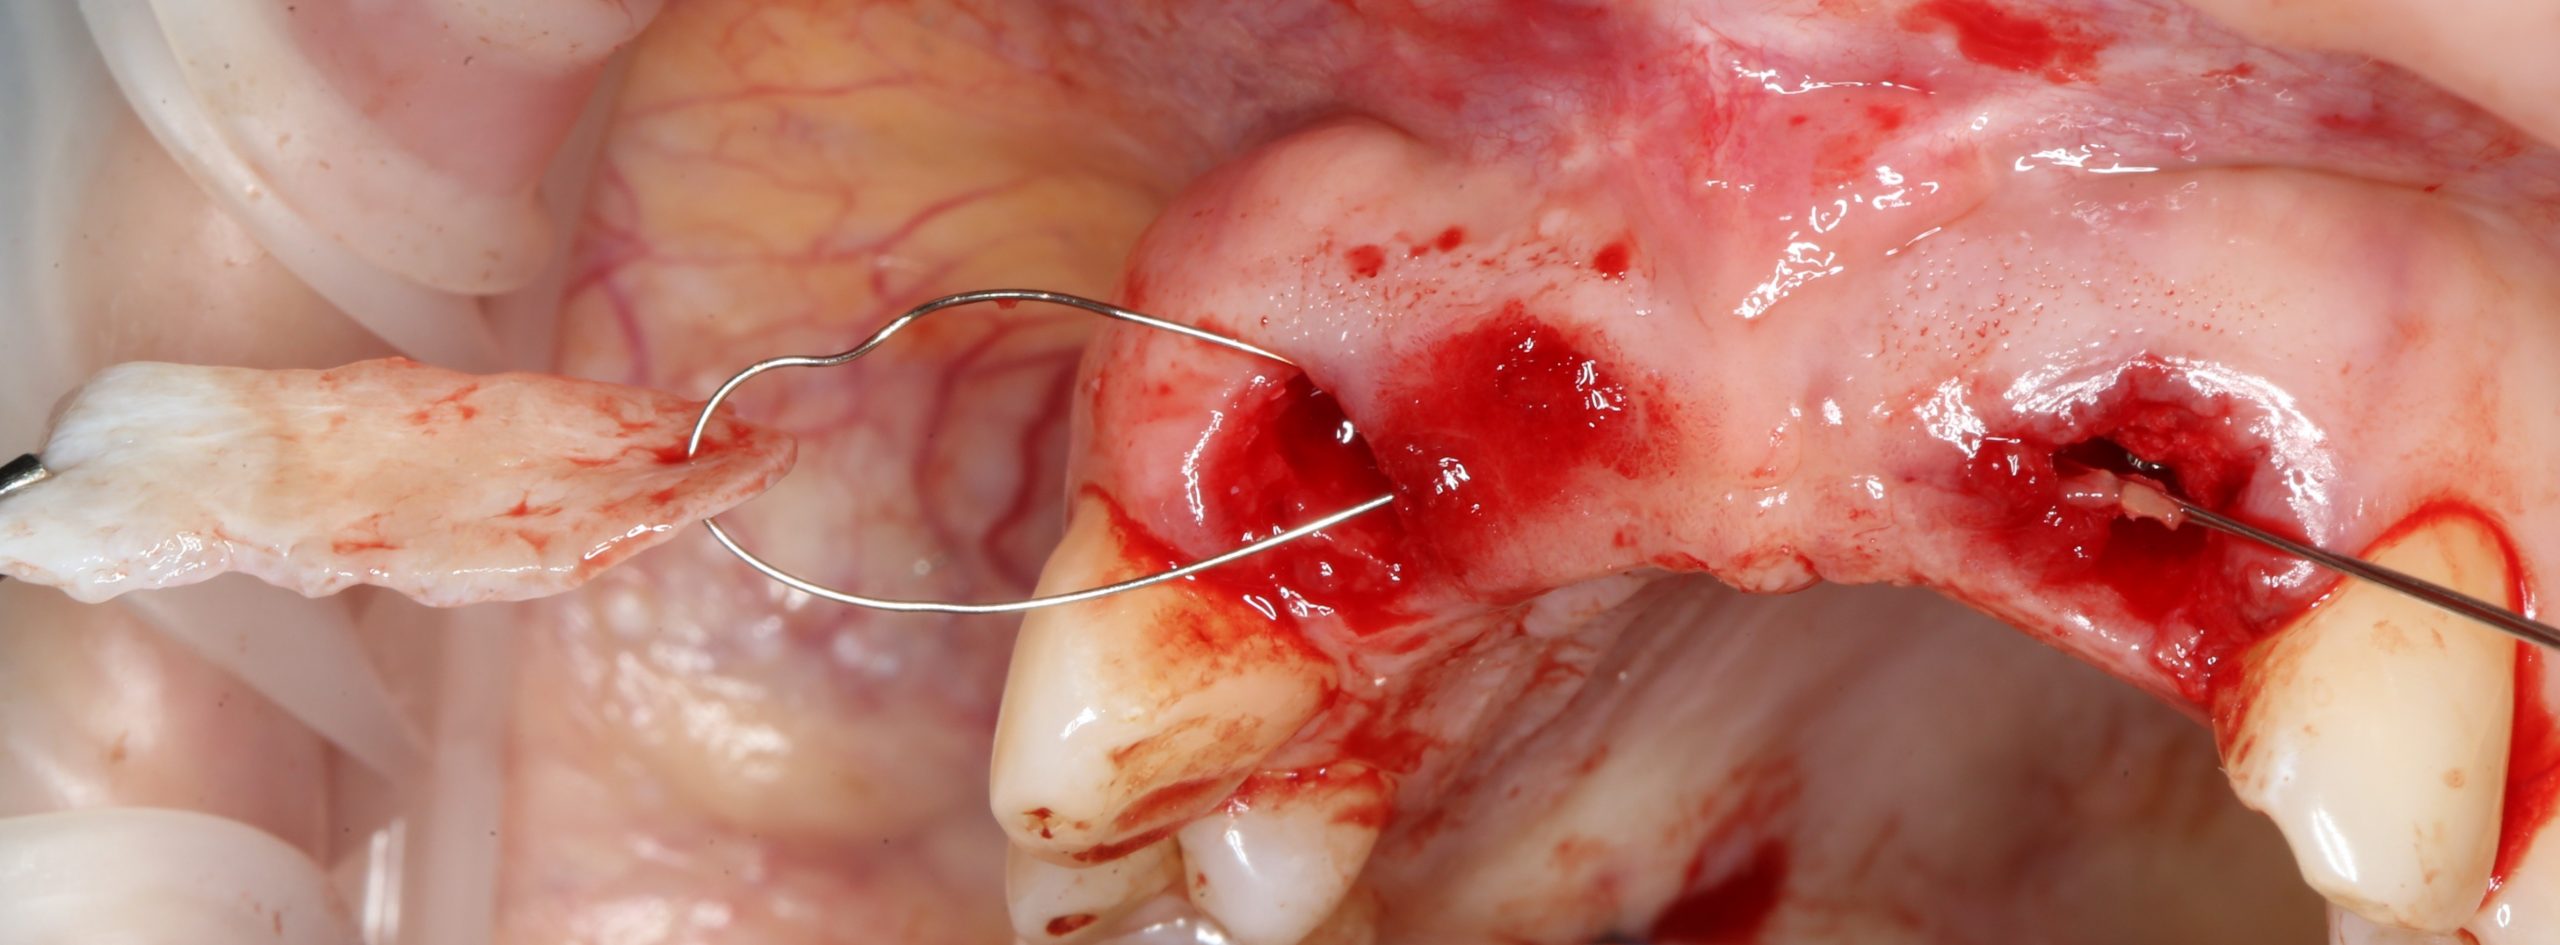

Следующий шаг — подготовка ложа под соединительнотканный аутотрансплантат или, проще говоря — под пересадку десны. Мы решили минимизировать травму, поэтому будем создавать подслизистый тоннель:

Это довольно просто, хотя и требуется известная аккуратность. Мы используем обычные инструменты для синуслифтинга:

Вы уже догадались, что мы не планируем дополнительных разрезов — весь объём работы мы проведём через лунки зубов. Таким образом, мы снизим травматичность нашей операции и, как следствие, риск возможных осложнений.

Создание тоннеля в области центральных резцов занимает 10-15 минут. В последующем, мы проведём и зафиксируем в нём соединительнотканный аутотрансплантат, который создаст необходимый для эстетики объём мягких тканей:

Суть такова. Сначала мы проводим проволоку через тоннель:

Затем прокалываем ей аутотрансплантат и проводим конец со стороны нанизанного трансплантата обратно:

Таким образом, можно легко и малотравматично «протащить» аутотрансплантат любого размера в сформированный тоннель любой длины: